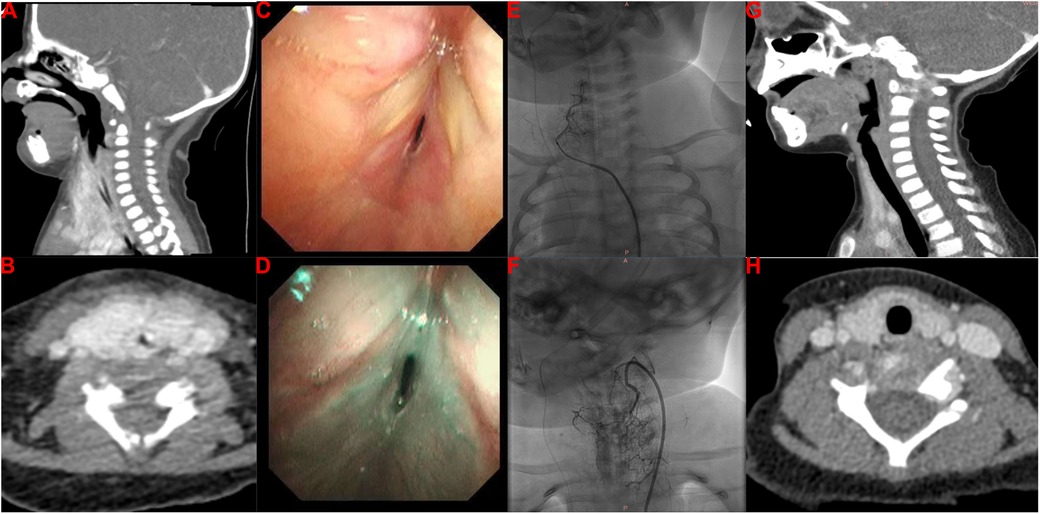

She was then transferred to our hospital to investigate the cause of the stridor in the larynx at 14 days old. On arrival, the physical examination found stridor with abnormal airway sounds, nasal flaring, head bobbing, and increased accessory muscle use. The patient’s respiratory rate was 70–80/min, her SaO2 was 88%–92%, and her heart rate was 160/min. The findings indicated that her clinical condition had deteriorated with severe breathlessness and progression to respiratory failure. Due to the early onset and persistence of the stridor and her progressive breathlessness, the congenital causes of stridor due to a structural abnormality were initially proposed, including laryngomalacia, tracheomalacia, vocal cord paresis/paralysis, vascular ring, bronchogenic cyst, laryngeal malformations, IHs, and subglottic stenosis. Contrast-enhanced computed tomography (CT) revealed circumferential tissue thickening with contrast enhancement around the subglottic area (Figures 1A,B), indicating the possibility of IH. Furthermore, flexible bronchoscopy identified airway IHs and an airway obstruction (Figures 1C,D). Due to the patient’s clinical manifestations and the imaging findings, the clinician proposed a diagnosis of airway IHs, which accounted for her deteriorating clinical condition. The guideline for the management of IH by the American Academy of Pediatrics strongly recommends clinicians use oral propranolol as the first-line therapy for IHs requiring systemic treatment (grade A, strong recommendation) (6). A surgical intervention may be recommended as a treatment option in selected IHs (grade C, moderate recommendation) (6). Notably, with the advent of β-blocker therapy, surgical interventions are used less frequently. The previous gold standard therapy for life-threatening IHs was systemic or intralesional corticosteroids (7, 15, 16). Therefore, corticosteroid therapy is also recommended for IHs in specific settings, such as in patients with IHs who present with contraindicated, poorly tolerated, or ineffective β-blocker therapy. Complete informed consent regarding the treatment plan was obtained from the patient’s legal guardian, and they chose a combination therapy of oral propranolol and corticosteroids. The combination therapy of oral propranolol (gradually increased to 2 mg/kg twice a day) and corticosteroids (2 mg/kg twice a day) was prescribed for 2 weeks after the multidisciplinary team's discussion. Regrettably, she still required invasive mechanical ventilation after this 2-week therapy. After the multidisciplinary team's discussion, endoscopic resection was carried out by a pediatric otolaryngologist, aiming to resolve her airway obstruction at 30 days old; however, this surgical intervention failed. We then explained the patient's current condition and prognosis to the patient's guardian in detail. Finally, her guardian agreed to transcatheter interventional sclerotherapy (Figures 1E,F). The feeding arteries of the lesions were embolized using penile vascular anomalies (PVAs) (300 µm) and iodinated oil to reduce the blood flow rate. Bleomycin (0.5 mg/kg) was injected as the sclerotherapeutic agent. Encouragingly, this additional treatment resolved the patient’s clinical symptoms, and the invasive mechanical ventilation was withdrawn 7 days later. At 60 days old, she was discharged home and received follow-up at our outpatient clinic, undergoing oral propranolol therapy. One year later, a neck CT identified that the circumferential tissue thickening with contrast enhancement around the subglottic area had been resolved (Figures 1G,H), and she did not have any clinical symptoms of airway obstruction.

Figure 1. Imaging findings of our patient with infantile hemangioma with airway obstruction. (A,B) Contrast-enhanced CT imaging reveals a thickening of circumferential tissue with contrast enhancement around the subglottic area. (C,D) Flexible bronchoscopy identifies IHs in the airway and an airway obstruction. (E,F) Transcatheter interventional sclerotherapy is performed. (G,H) Repeated contrast-enhanced CT reveals that the circumferential tissue thickening with contrast enhancement around the subglottic area was resolved with the treatment.